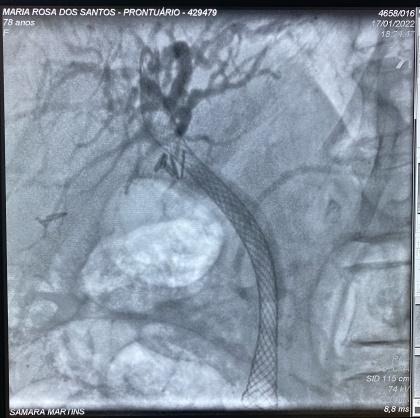

Paciente manteve assintomática e acompanhamento ambulatorial para programação de tratamento definitivo, que foi optado pela dilatação da via biliar (balão CRE 6-8mm) e inserção de prótese metálica auto-expansível totalmente recoberta (10 x 80mm) (Fig 5). O procedimento foi realizado 90 dias após a primeira CPRE sem intercorrências e optado pela retirada após 1 ano. A última CPRE foi realizada 12 meses após a inserção da prótese metálica no qual foi possível retirá-la, extrair o cálculo da via biliar proximal e obter uma colangiografia sem sinais obstrutivos ou extravazamentos ao final do procedimento (Fig 6).

Fig 5. Imagens colangiográficas da segunda CPRE: A. Imagem colangiográfica mostrando coledocolitíase proximal e subestenose em topografia de clipes; B. Imagem colangiográfica dilatação com balão em via biliar; C. Imagem radiológica da prótese metálica auto-expansível.